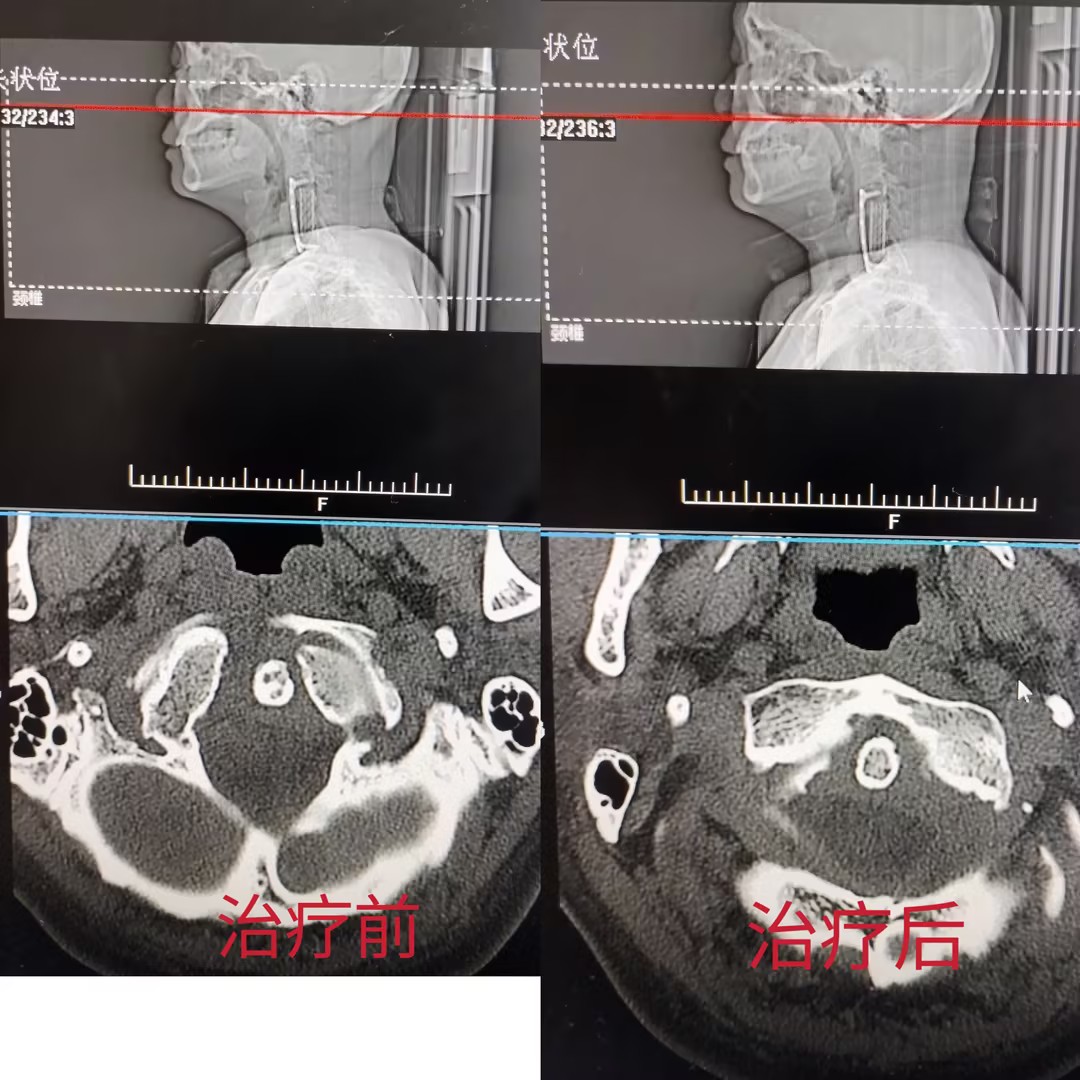

经过三次系统调理,老杨感觉轻松了不少。颈部的疼痛和沉重感明显减轻,活动范围也大了。更重要的是,复查的 CT 片子显示了他身体内在结构的变化:颈椎上端「齿状突」与两侧关节的间距不对称的情况得到了改善。这说明,治疗不仅缓解了症状,也在帮助他身体的力学结构向好的方向调整。